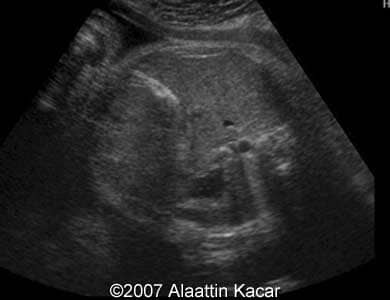

These are some images of a fetus with hyperechoic content of the gallbladder. We assumed presence of gallstones in the fetus.

Image 3: Transverse scan through the abdomen at the level of the gall bladder showing its hyperechoic content.